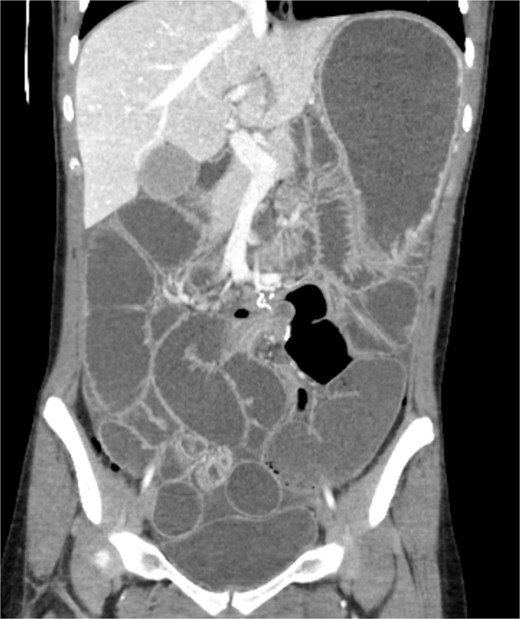

A 19-year-old female presented to the emergency department with complaints of epigastric abdominal pain, nausea, vomiting, and having passed no gas or bowel movements for 4 days. Her past medical history consisted of irritable bowel syndrome, gastroparesis, depression and anxiety, eosinophilic esophagitis, and opioid abuse. She did not take any medication for her depression and anxiety. Her past surgical history included upper and lower endoscopy and surgical ablation of genital warts. She has a significant family history of a brother who has ulcerative colitis. Upon physical exam, her abdomen was tympanic and distended. There was epigastric tenderness with no guarding or rebound tenderness. Due to concern for a bowel obstruction, a nasogastric tube was placed, and a computed tomography (CT) scan was done (Fig. 1). Imaging showed immense distension of the colon due volvulus at the splenic flexure with narrowing of the mesenteric vasculature and free fluid in the abdomen. The patient was taken for an exploratory laparotomy emergently with a preoperative diagnosis of a large bowel obstruction due to internal hernia versus volvulus. During the operation, it was found that the distal transverse colon was the point of obstruction and showed scarring with dilatation proximal to the narrowing, and there was no internal hernia identified. An extended right colectomy was performed with ileocolic anastomosis. She had a return of bowel function on postoperative Day 4. Six days post-operation, the patient began to have nausea and vomiting and had not had a bowel movement in 2 days. Eight days post-operation, a CT scan was performed that illustrated proximal small bowel dilatation (Fig. 2). With concerns of another bowel obstruction, an exploratory laparotomy was performed. During the operation, a dilated small bowel and a twisted sigmoid colon were found consistent with a large bowel obstruction secondary to sigmoid volvulus. A completion colectomy with end ileostomy was performed.

CT of the abdomen performed on Day 1 of admission. Shows colonic distension with volvulus at the splenic flexure.